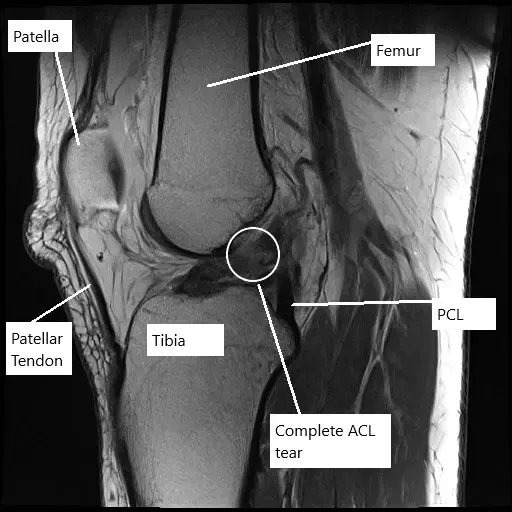

MRI of the left knee showing complete tear of the ACL.

Radiological study in the form of an MRI suggested a complete tear of the ACL along with complex tears of both the medial and the lateral meniscus. The patient desired to be athletically active and to continue her job without any episodes of instability.